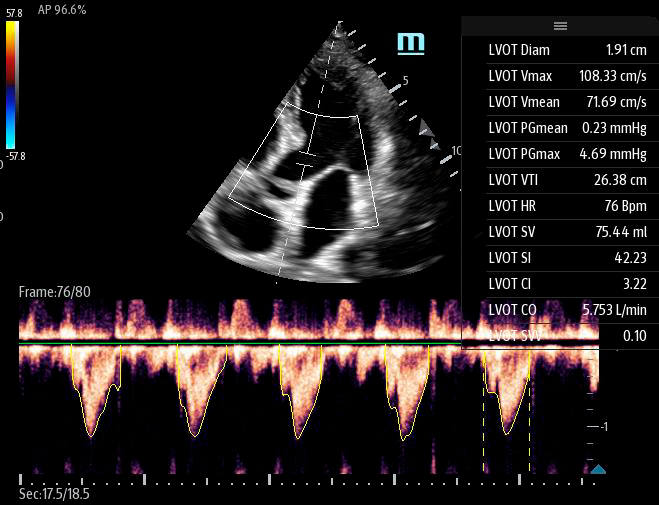

Автоматическая оценка потока выносящего тракта – Smart VTI

Чтобы использовать уравнение, нужно получить поток выносящего тракта левого желудочка в PW допплере — это достаточно кропотливая работа. В ультразвуковых системах Mindray Resona i9 эта задача решается автоматической оценкой потока выносящего тракта – Smart VTI.

Доктору остается получить 5-ти камерное сечение сердца и нажать одну кнопку на сенсорном экране. Прибор сам выберет расположение контрольного объема, получит спектрограмму и обведет спектр с расчётом всех показателей. Быстро и эффективно.